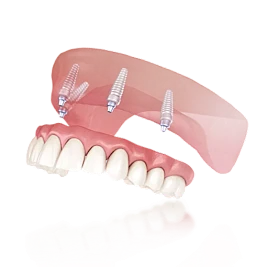

Мы лечим кариес, пульпит, периодонтит, восстанавливаем разрушенные зубы, возвращая не только здоровье, но и эстетику. Подход к каждому пациенту — индивидуальный: с точным планом, прогнозом и фиксированной стоимостью.

- Мы решаем сложные случаи сообща: имплантологи, ортопеды, терапевты и ортодонты действуют слаженно, как одна команда.

- Если вы ищете современную стоматологию в Перми, где можно пройти весь путь лечения — от диагностики до установки протезов или исправления прикуса — в одном месте, без потери качества и времени, вы попали по адресу.